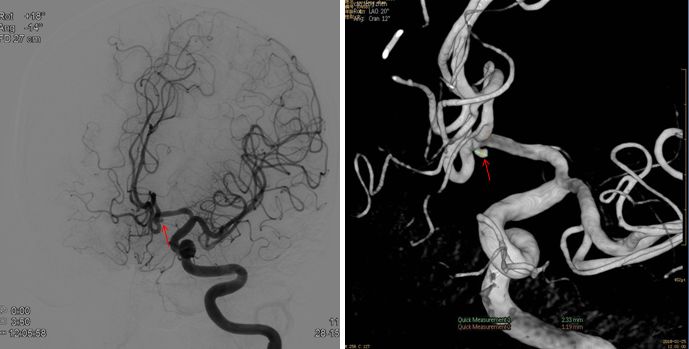

三次造影动脉瘤变化(相差三周时间)

2-13 —动脉瘤栓塞(瘤体明显增大)